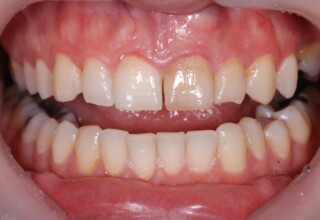

Αποκατάσταση διαστημάτων μεταξύ κεντρικών και πλαγίων τομέων

Τα διαστήματα έχουν δημιουργηθεί κυρίως λόγω των στενών πλαγίων. Μετά την ολοκλήρωση της ορθοδοντικής θεραπείας τα διαστήματα “έκλεισαν” με την τοποθέτηση δύο αποκαταστάσεων σύνθετης ρητίνης.